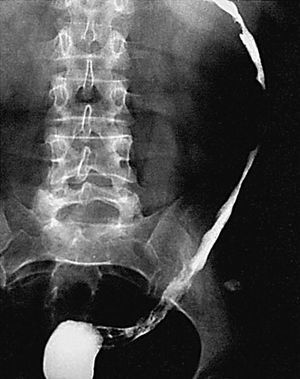

Al nivel de íleon terminal el espasmo justifica el signo de "la cuerda" (fig. 6). En relación no sólo con el espasmo, sino con una proliferación fibroadiposa del mesenterio aparece el signo del "asa orgullosa" en el estudio con bario, cuyo sustrato fisiopatológico ilustra la TC (fig. 7).

Fig. 6.--Enfermedad de Crohn, fase activa inflamatoria. (A) En el tránsito baritado: signo de "la cuerda" a nivel del íleon terminal. (B) La correlación en tomografía computarizada (TC) muestra engrosamiento mural, hiperemia y estratificación.